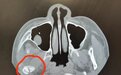

口腔颌面外科接诊医生立即查看患儿情况,进行CT检查,没想到这一摔竟导致丽丽右侧髁状突骨折。

髁状突位于颞下颌关节窝内,是下颌骨易发生骨折的部位之一。髁状突的损伤会导致张口受限,影响下颌的生长,甚至出现严重的面部畸形。

丽丽正处于快速生长发育期,而髁状突又是下颌骨发育的中心之一,处理不当将会严重影响后期的咬合关系与咀嚼功能,影响儿童面部发育。由于患儿年龄小,骨折位置偏高,接诊医生决定采用保守治疗的方式,通过髁状突塑形和功能改建,帮助患儿恢复下颌功能。